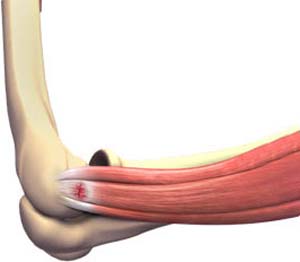

Tennis Elbow

Tennis elbow is a common name for the elbow condition lateral epicondylitis. It is an overuse injury that causes inflammation...